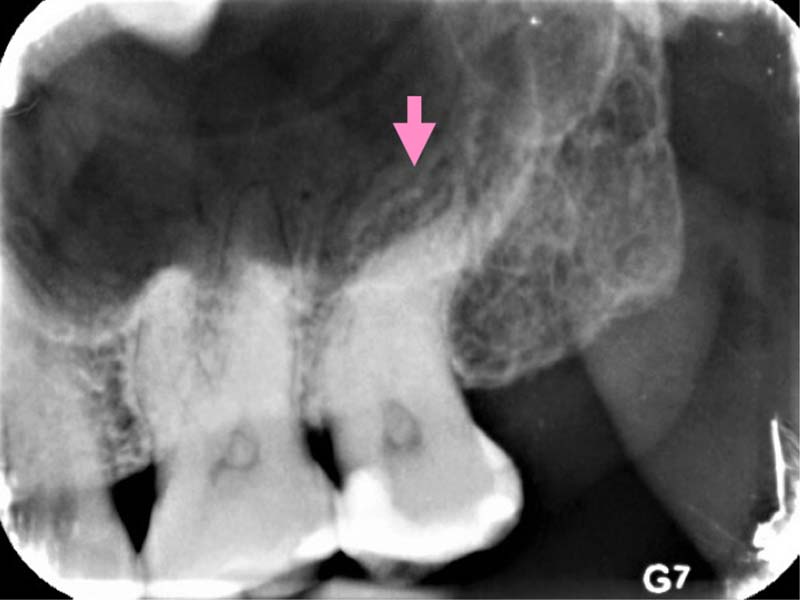

圖例為案例分享:

深度填補過後,持續冷熱敏感

依照症狀及顯微鏡下觀察,移除部分牙隨組織

術後三年追蹤檢查,狀況良好